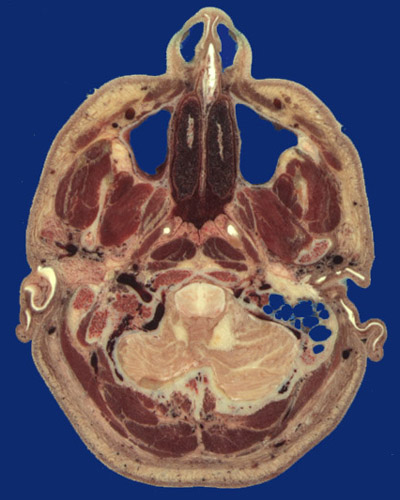

Identify the following regions in the image above: Nostril - Nasal septum - Middle nasal concha - Maxillary sinus - Mandibular coronoid process - Mandibular condylar process - Mandibular ramus - Nasopharynx - Pharyngeal tonsil - Eustachion tube - External acoustic meatus - Tragus - Antihelix of pinna - Mastoid air cells - Pons - Cerebellum - Levator labii superioris - Zygomaticus - Masseter - Medial pterygoid - Tensor veli palatini - Levator veli palatini - Longus capitis - Rectus capitis anterior - Splenius capitis - Rectus capitis posterior major - Semispinalis capitis - Trapezius - Occipitalis - Internal jugular vein - Jugular foramen - Base of occiput - Retromandibular vein